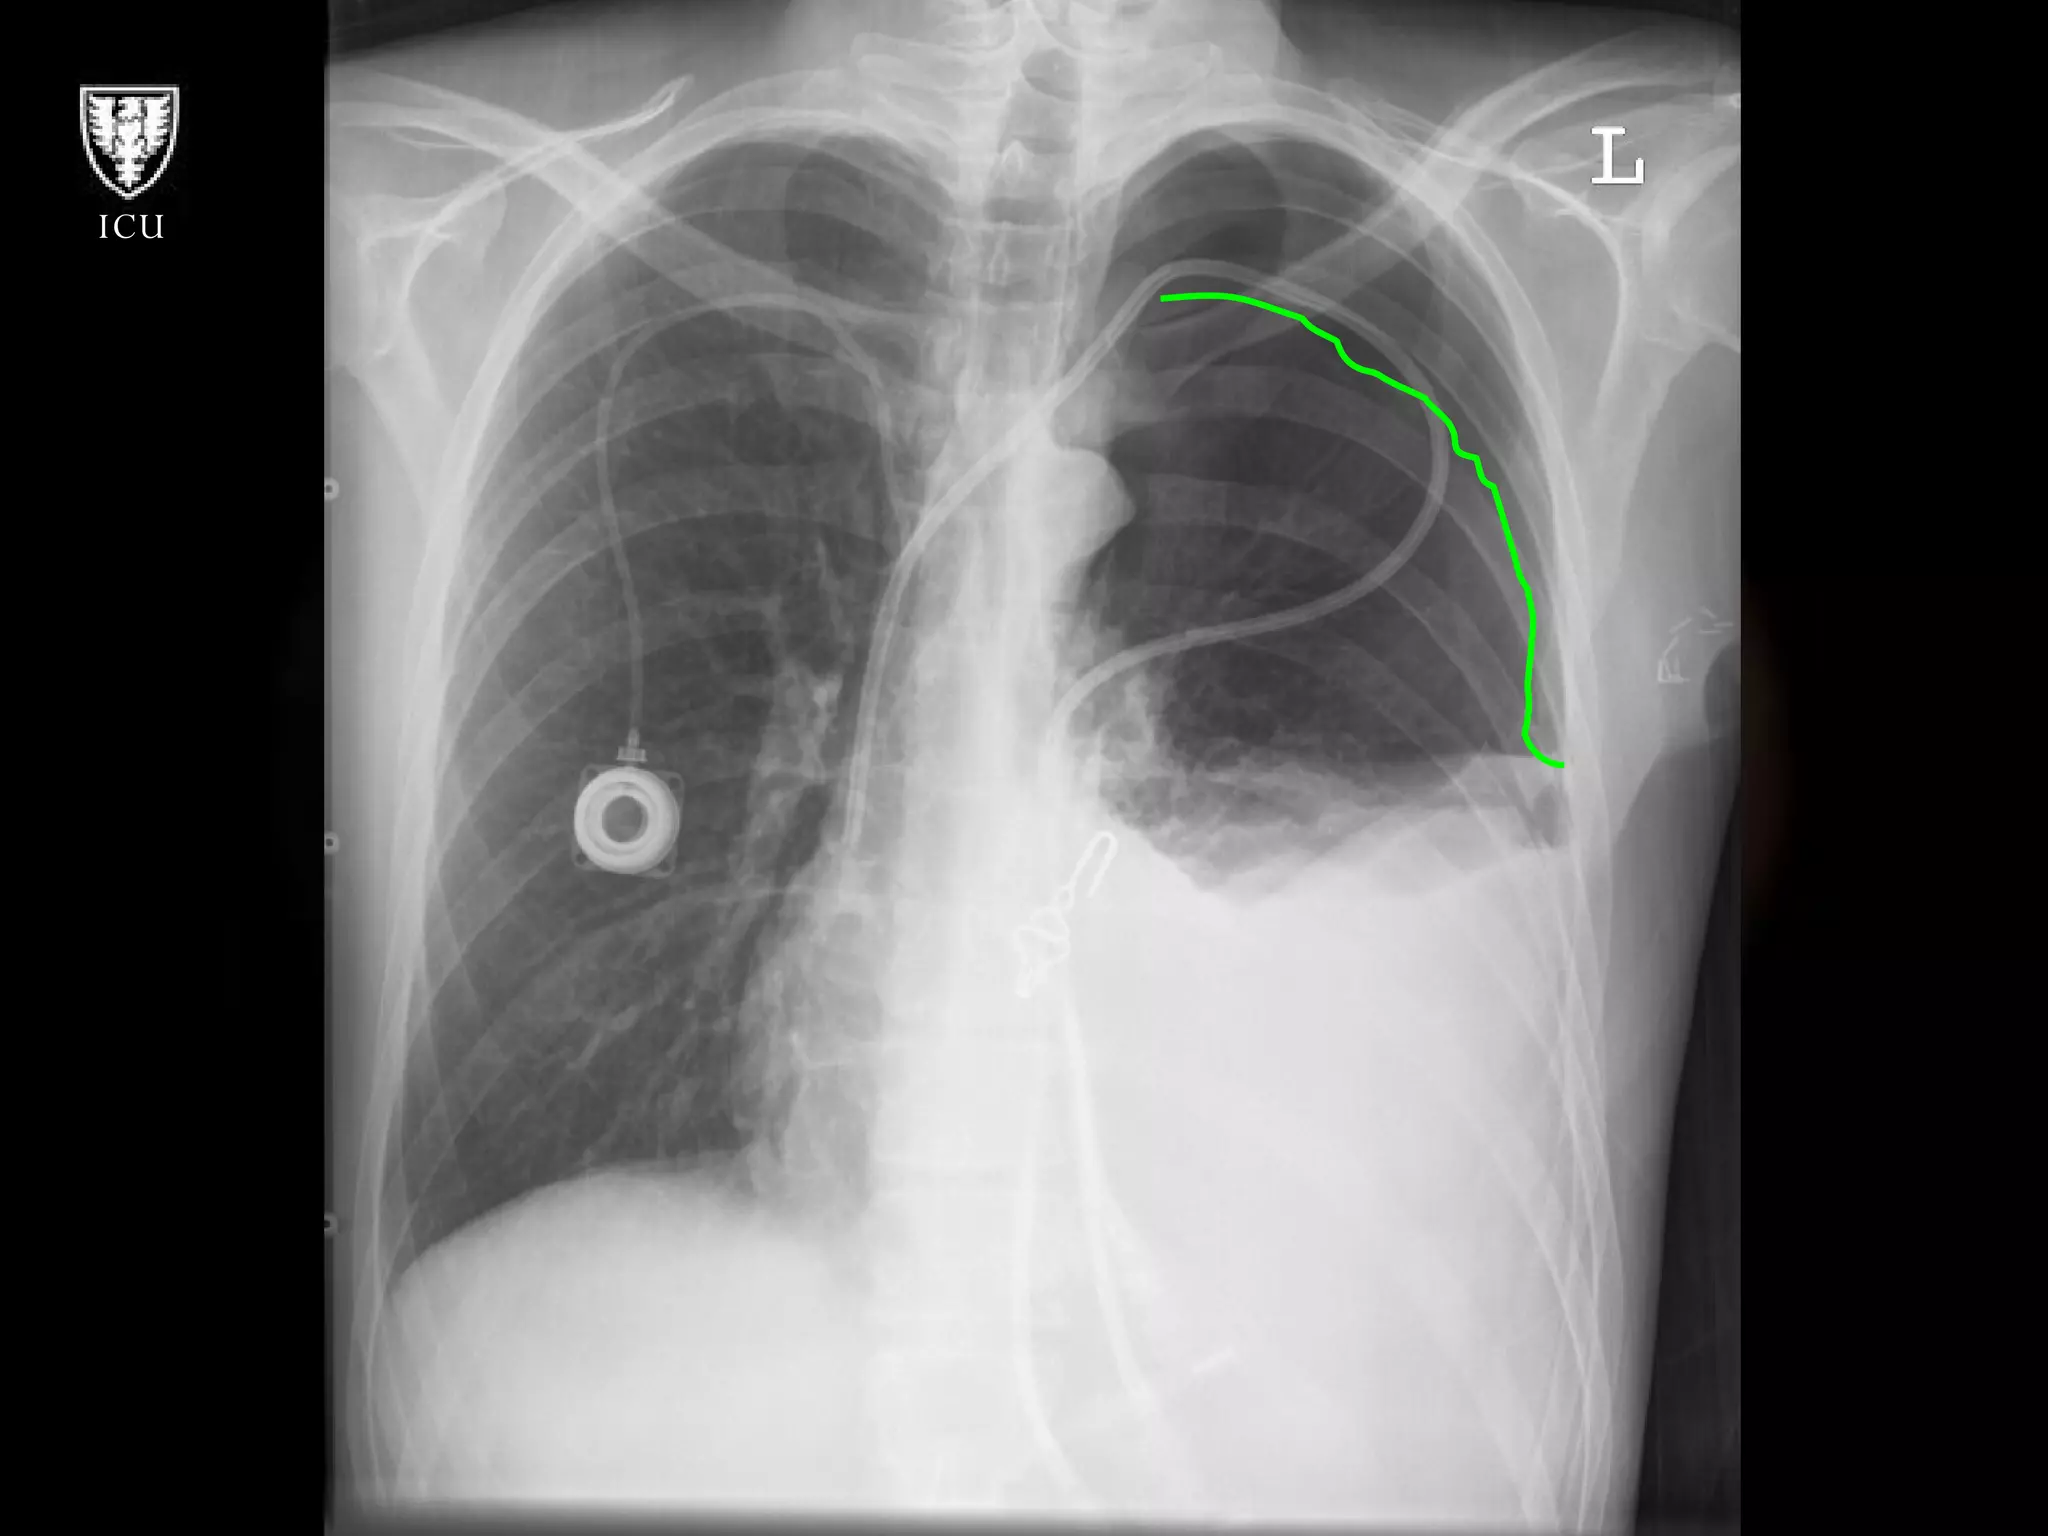

Subclavian going  In wrong direction

Carotid Artery Insertion